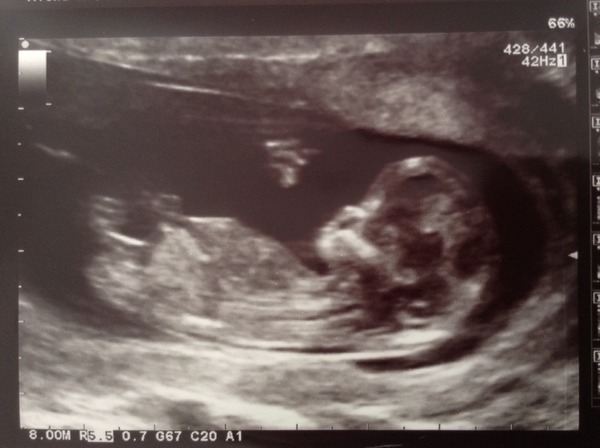

I wanna play! Here's the Prulet...

Oh the Prulet is so cute!